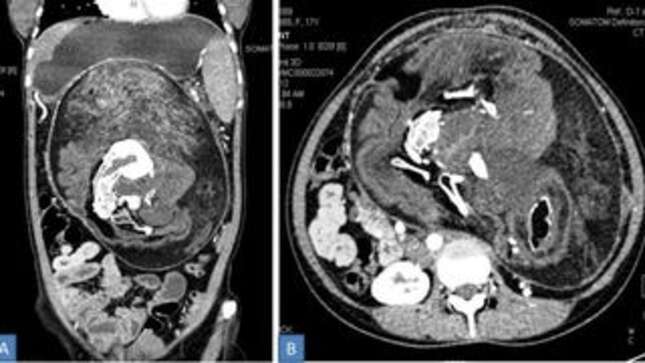

On the initial physical examination, the lump was suspected to be a tumor. Which in a sense, it was. But when they ran a CAT scan on the lump, they found deposits of calcium that looked like “the shape of vertebrae, ribs and long bones,” and the more grisly truth was finally uncovered. The doctors then went to work removing it.

According to the report, the contents of the tumor “consisted of hairs, mature bones and other body parts.” These body parts included “multiple teeth and structures resembling limb buds.” Its sheer size—36×16×10 centimeters—would also make it the largest ever found in a case of adult fetus in fetu.